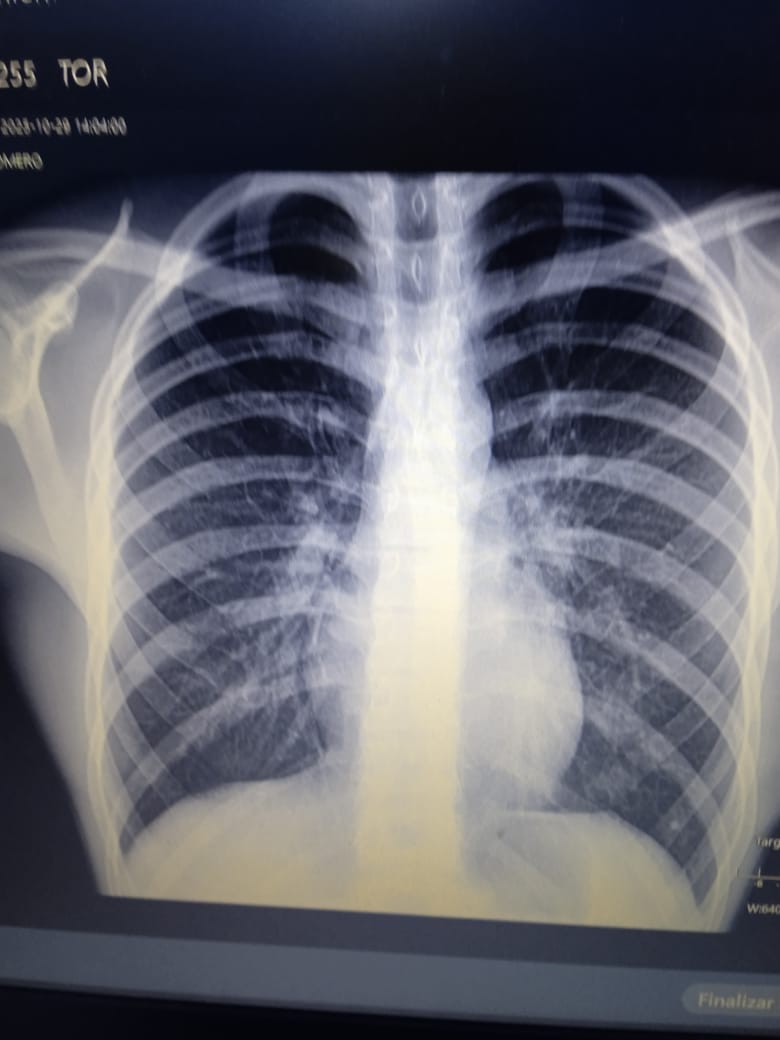

Su consejo fue una orden llena de esperanza: Vaya al hospital mañana, repita los exámenes y búsqueme. Les haremos placas de tórax. Esa intervención no fue casual; fue el cable a tierra que necesitaba para no desconectarme por completo.

Era la confirmación de que, incluso en la soledad más absoluta, la bondad humana puede aparecer en las formas más insospechadas. Los resultados definitivos de algunos exámenes tardarán, pero por ahora tenemos un diagnóstico claro y un tratamiento que seguir. La neumonía bilateral en mis dos niños pequeños y la bronquitis en mi hijo mayor son condiciones serias, pero por fin tienen un nombre y un camino a seguir.

Her advice was a hopeful command: Go to the hospital tomorrow, repeat the tests, and find me. We'll take chest X-rays. That intervention wasn't a coincidence; it was the anchor I needed to keep from completely disconnecting.

The final results of some tests will take time, but for now we have a clear diagnosis and a treatment plan. Bilateral pneumonia in my two young children and bronchitis in my older son are serious conditions, but they finally have a name and a path forward.